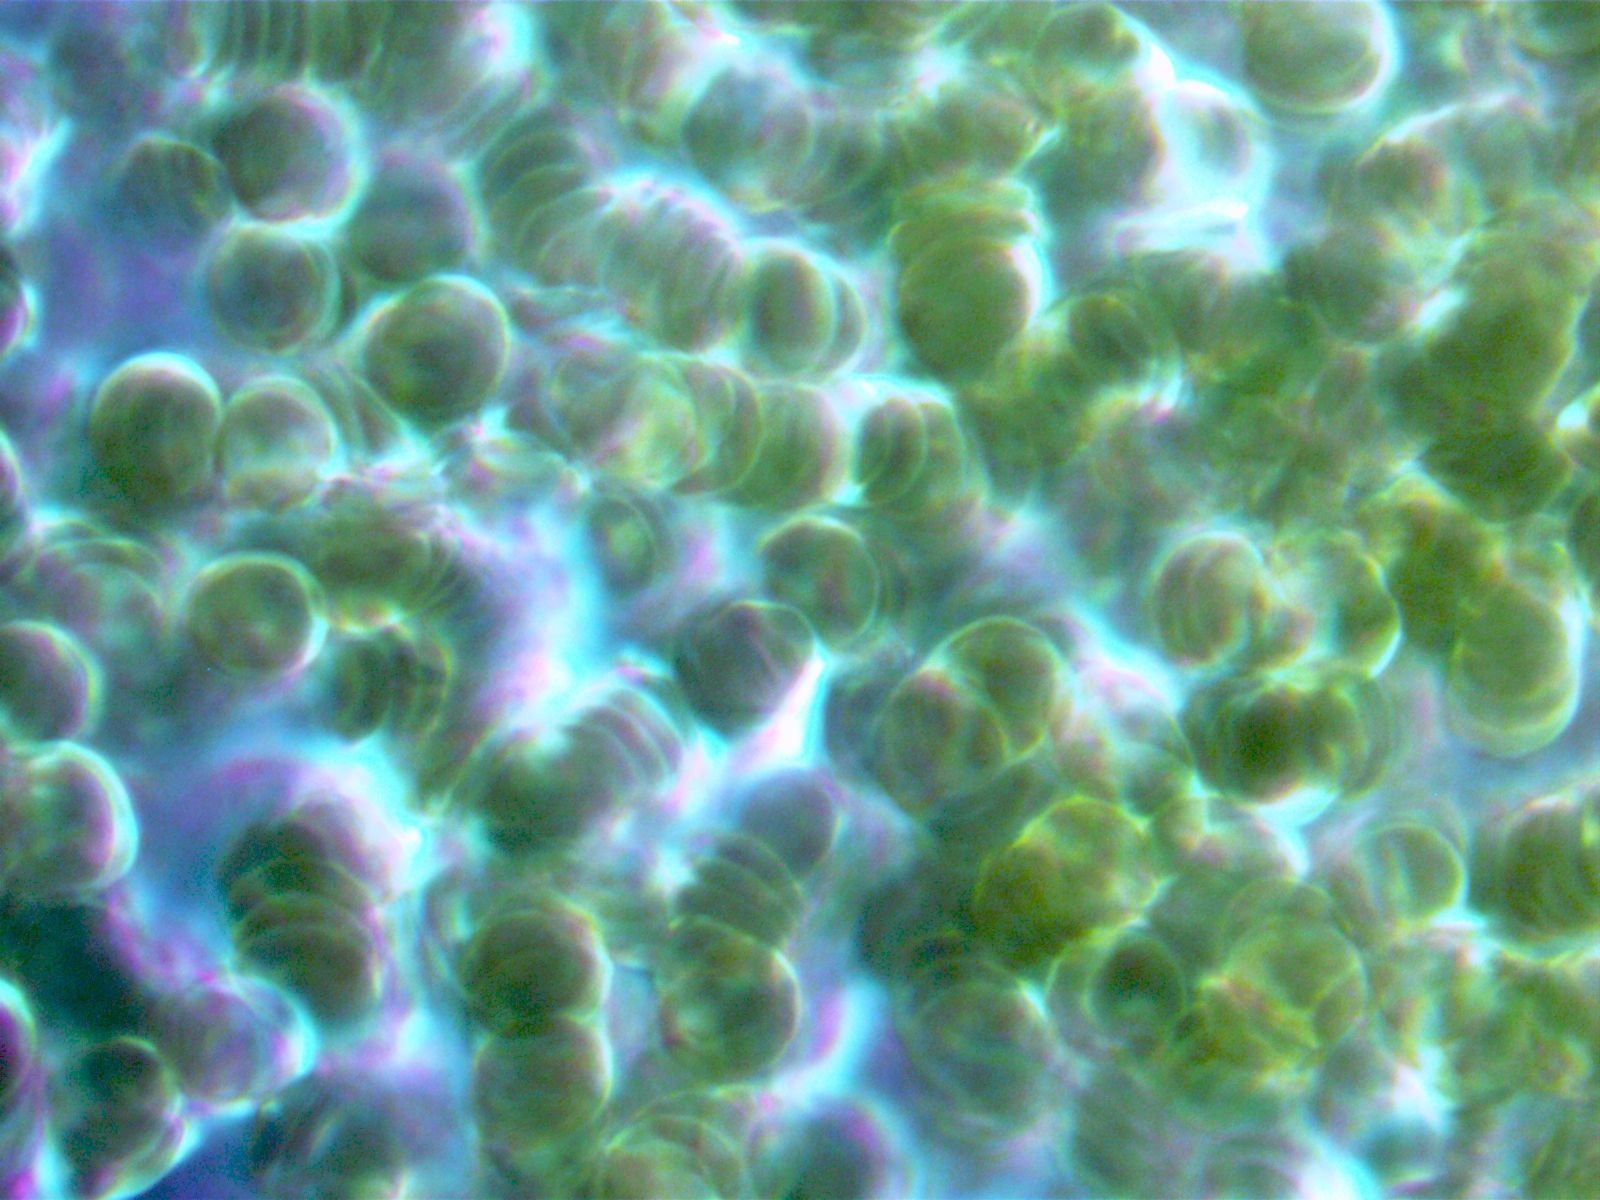

Die Dunkelfeldmikroskopie

Die Dunkelfeldmikroskopie ist eine spezielle Variante der Lichtmikrosokopie. Diese spezielle Untersuchungsmethode des Vitalbluts gibt tiefe Einblicke in die biochemischen Prozesse des Körpers und ist eine ideale Ergänzung, sowohl zu den herkömmlichen schulmedizinischen Laborblutbefunden, als auch zur bioenergetischen Körpermessung mit Global Diagnostics / Vitalfeldtherapie.

Während bei den üblichen Labor-Blutbildern die Bestandteile des Blutes quantitativ bestimmt werden, zeigt das Dunkelfeld Aktionen und Interaktionen der Blutzellen, sowie deren Form und Beschaffenheit. Dies ermöglicht nicht nur Beurteilung von akuten Erkrankungen, sondern auch Dispositionen für gesundheitliche Probleme, bevor sie sich in Symptomen manifestieren.

Für die Dunkelfeldmikroskopie genügt ein einziger Blutstropfen aus der Fingerbeere. Dieser wird in Ihrem Beisein über das Dunkelfeldmikroskop analysiert und in Echtzeit zum Mitschauen auf einen Bildschirm übertragen -Bei vorliegenden Belastungen können wir in einem gemeinsamen Gespräch ein grundlegendes Therapiekonzept entwickeln.